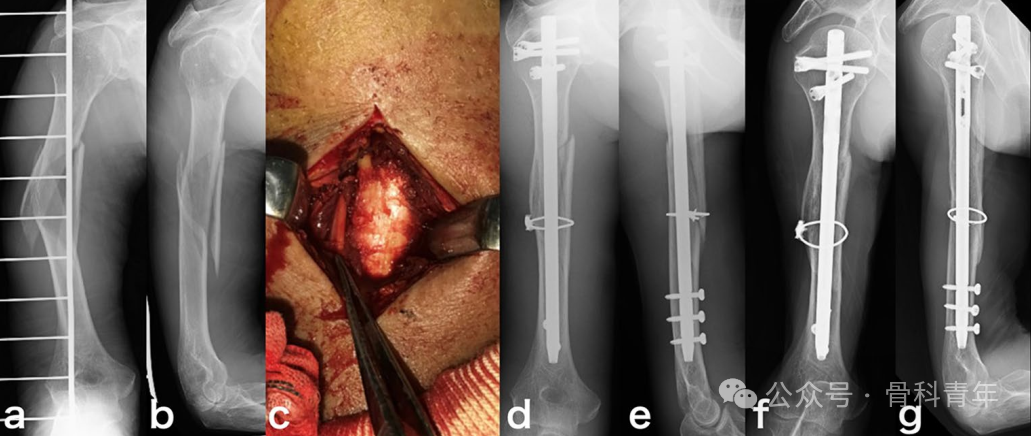

股骨干骨折

文章纳入了37例粉碎性股骨干骨折病例,16例行钢丝环扎辅助固定,21例行单纯髓内钉固定:

文章结果表明,钢丝环扎组,在骨科愈合时间,术后12月和24月HSS评分、HHS评分,骨折愈合率上均存在明显优势。建议对粉碎性股骨干骨折行钢丝环扎辅助固定。

在另一篇对股骨干粉碎性骨折钢丝环扎的固定研究中,尽管在骨折愈合率和并发症上未发现统计学差异,但钢丝组骨折复位较非钢丝辅助复位组好,且并不增加并发症风险。钢丝环扎具有非劣效应。